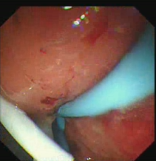

一例位置刁钻的胰腺假性囊肿,向大家汇报一下:

这个假性囊肿穿刺位置有点刁钻

超声下的视野像一个水壶

从小囊穿刺,但是镜身位置不容易固定

扩张后置入内外引流

术毕